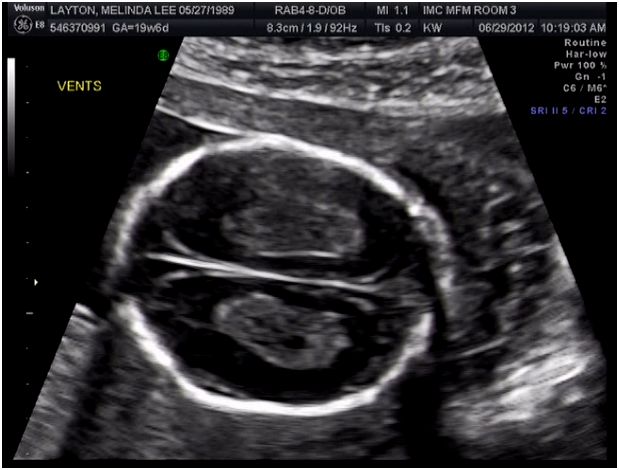

So I have decided it's time to come back to the blogging world. But for a good reason. Jake and I are having a baby! A cute little boy to be exact, and we are so excited! We got to see him for the first time yesterday and thought it would be fun to let you see.

Here he is!

Apparently he doesn't like to be bothered...

Here is a cute profile of him with his hand near his mouth.

I loved this shot. He's already got a great looking brain. Maybe he will have a "photographic memory" like his dad. (Jake likes to think he does anyways)

For all of you who keep asking for a photo of me, and although I feel very strange taking these profile shots, here it is. When I took this I thought I was 19 1/2 weeks, but after the Dr's visit apparently I am only 17 1/2 weeks. Bummer. But actually it is great news for me because I will probably be able to finish my entire last semester Physical Therapy internship before he is born. That way I will be able to graduate on time! My new due date is December 3 and my clinical rotation will end around November 16 because I will be starting it a week early. Hopefully I can keep going strong until then!